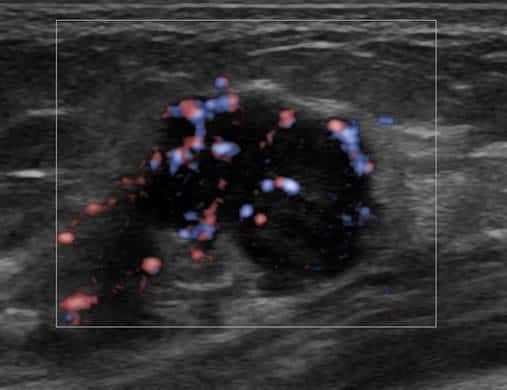

Ung thư vú

» Thông tin: Nữ giới – 55 tuổi.

» Lâm sàng: Khối tuyến vú.